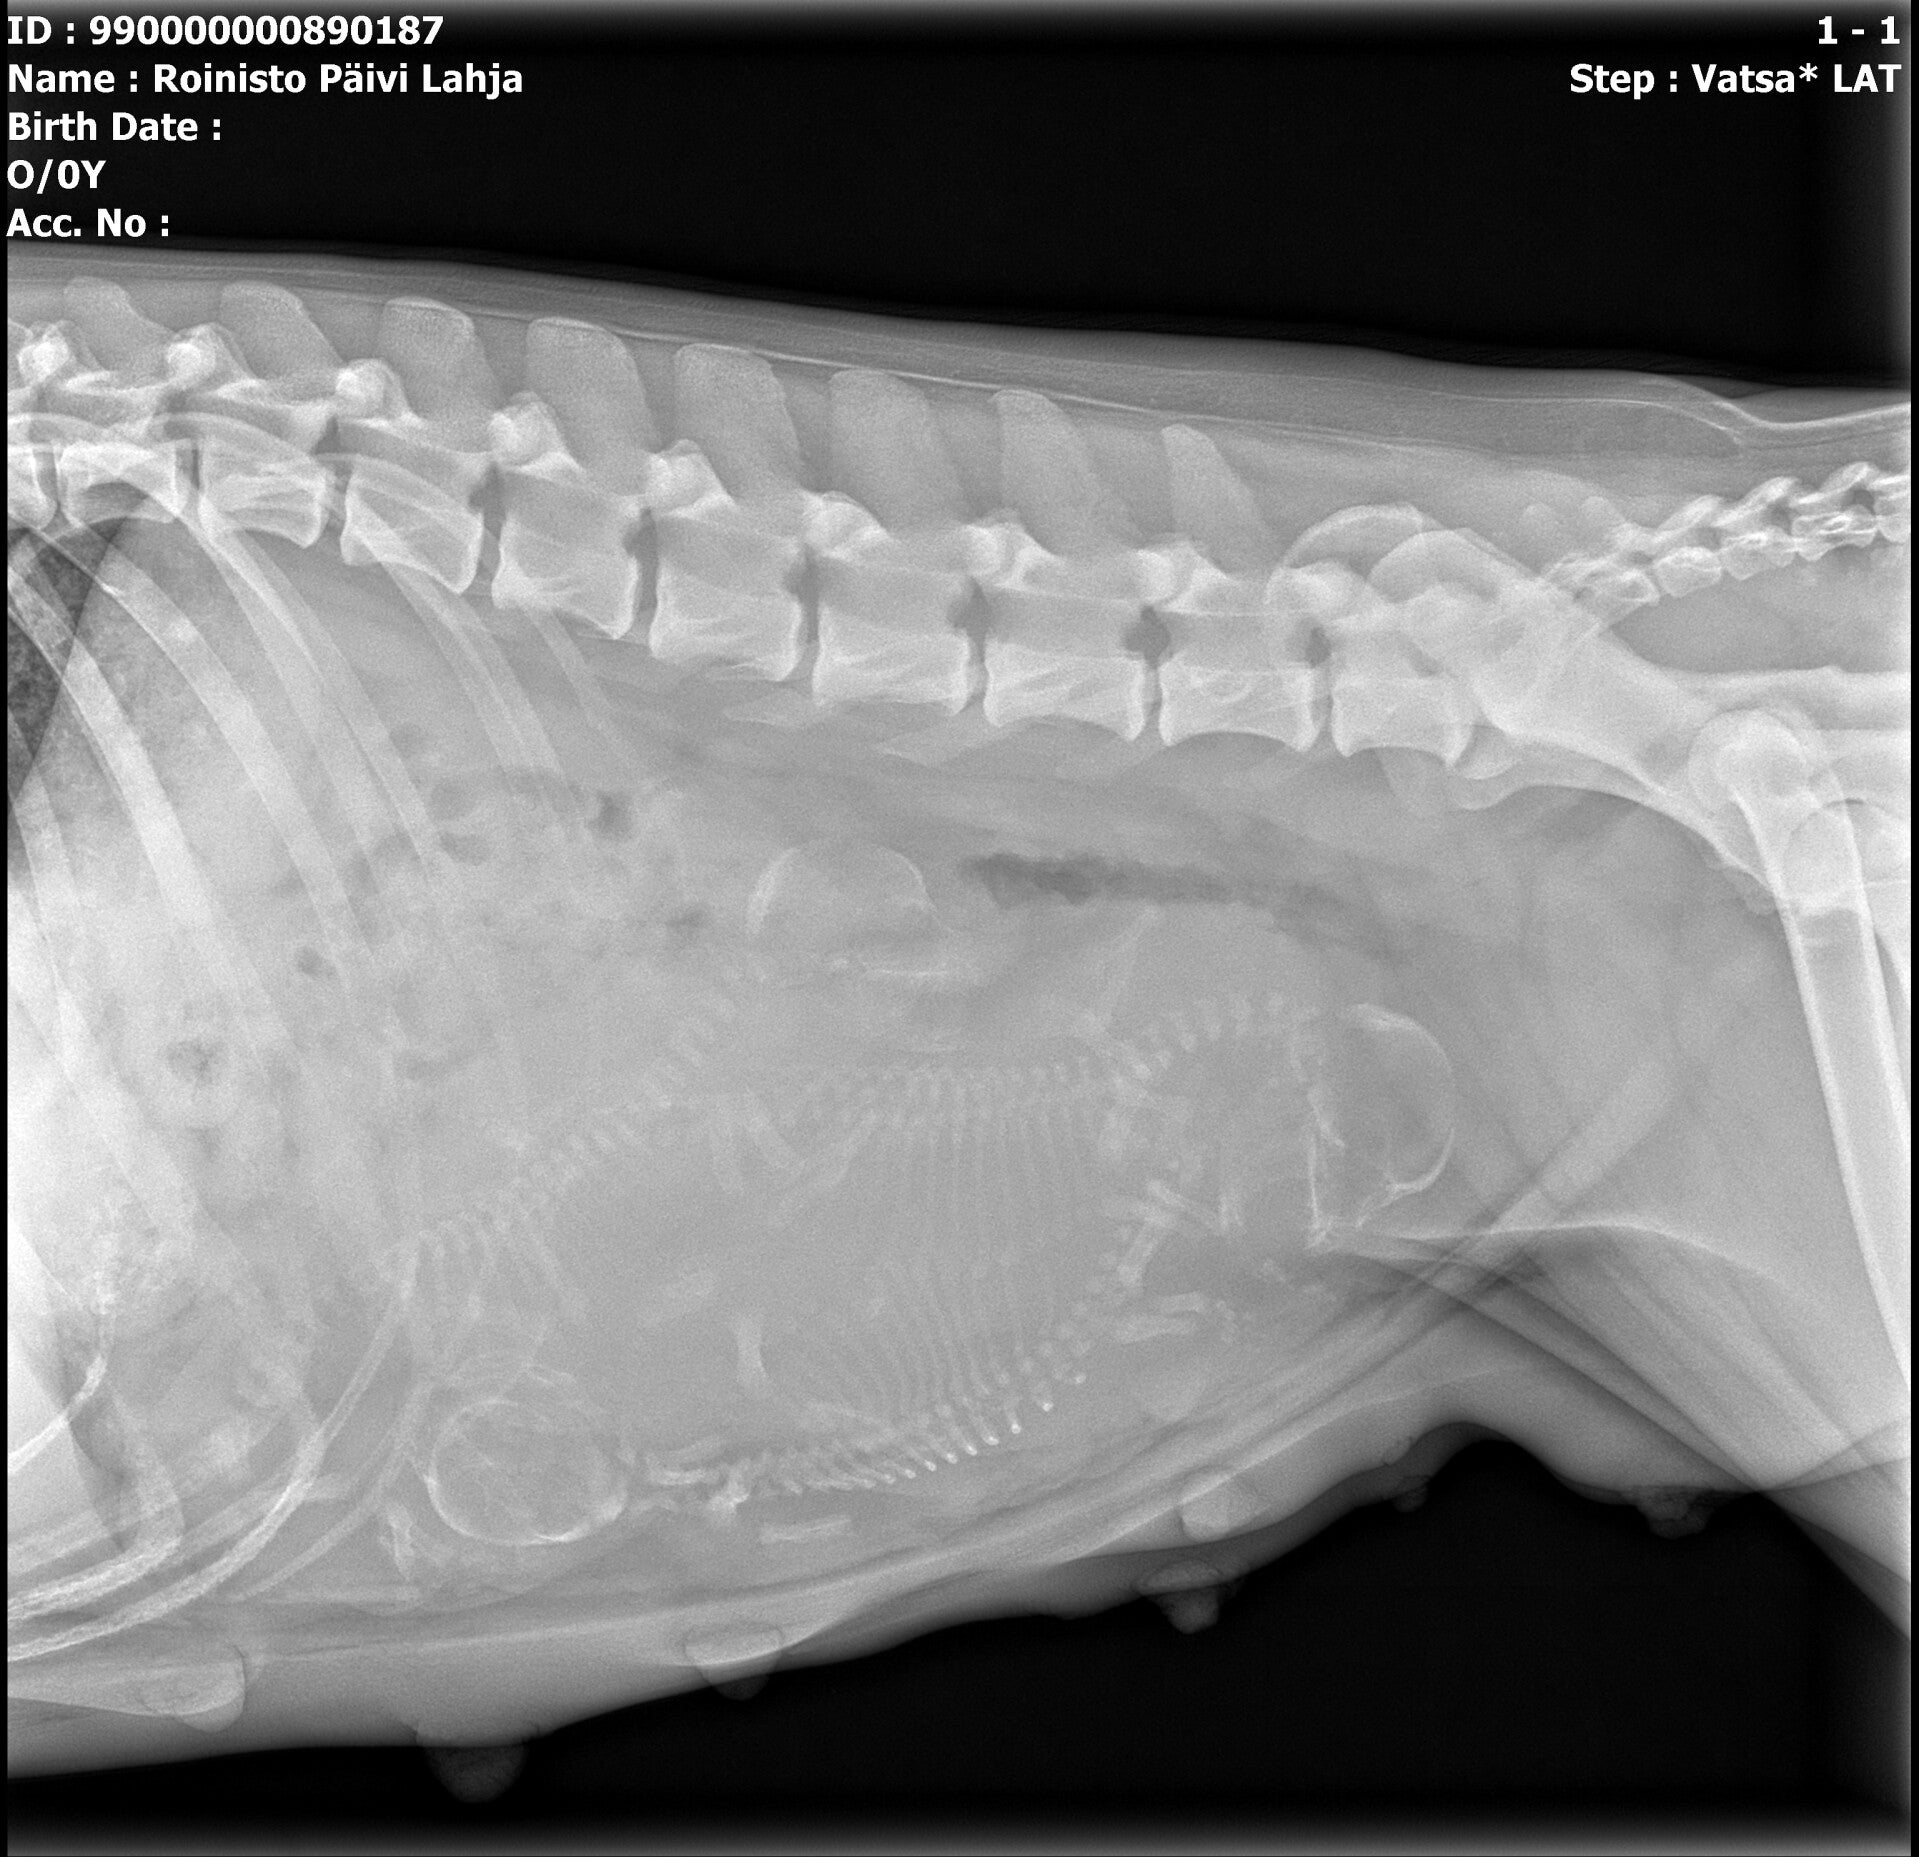

Ihanainen Elle "Lahja" Suoritti luonnetestin pistein 118

s.2.6.2022   FI37966/22

SP1 LTV0 C/D